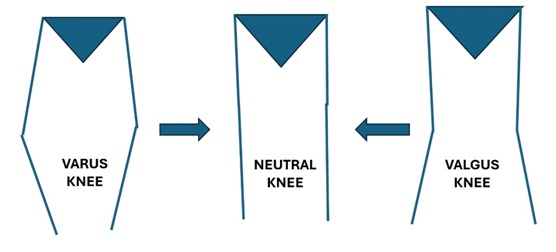

A knee replacement surgery is designed to provide pain free improvement in quality of life. The important determinant is alignment, ligament balance and good fixation of the implant. Since there is no one alignment that is superior to another the default standard has been “MECHANICAL NEUTRAL” approach where whatever the starting points- the aim is to get to a straight line. This approach potentially reduces the ultimate satisfaction rates

Recently, knee alignment has been found to fall into one of 9 categories and each patient who undergoes a knee replacement would fall in one of these 9 categories. The aim of conventional TKA was to get a perfect 180-degree alignment on standing view which would correspond to CPAK category V. In spite of good alignment, a section of patients arestill unhappy, and the hypothesis was that the change of CPAK category leads to dissatisfaction.

The principle of robotic TKA is to move patients towards better alignment but retaining the patient in the same CPAK category so that there is improvement in the patient’s functional outcome and satisfaction rates. This approach is to ensure that “One size fits all” approach is not undertaken and truly individualizing the care to each patient’s needs. This technique and philosophy were advocated by Dr. Johan Bellemens group in 2021 and now evidence is emerging that the CPAK philosophy helps patient achieve better satisfaction rates and our experience of more than 100 robotic knees are pointing towards the same outcome.